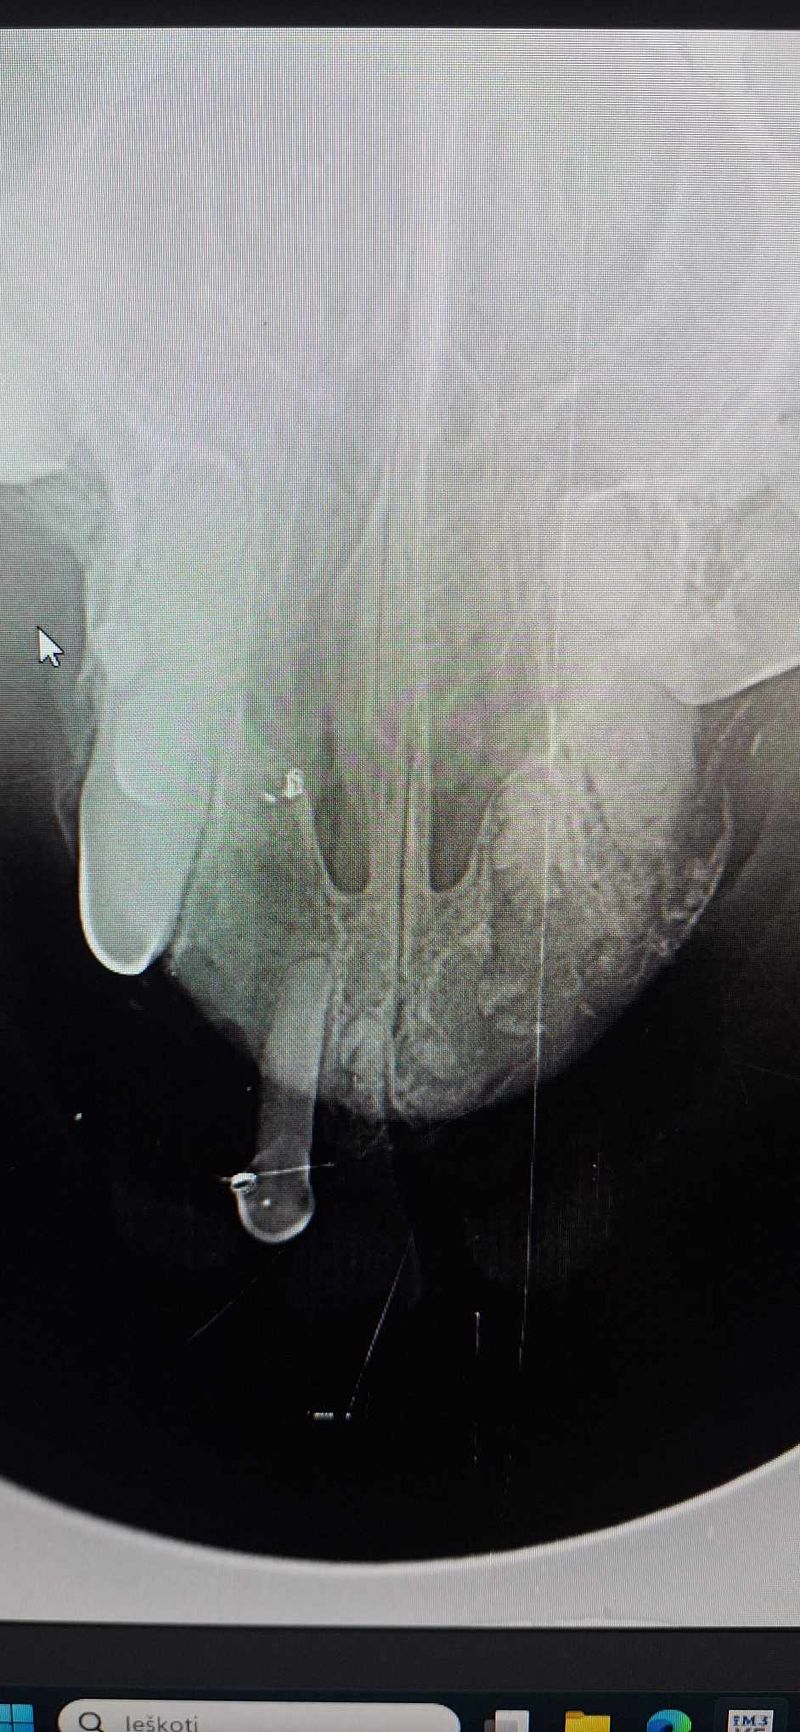

Policijos pareigūnų kovo 16 d. atvežtas sužalotas šuniukas į Šiaulių veterinarijos centrą, kovo 17 d. jau išoperuotas. Atsirado ir šeimininkai (Maksiuko..).